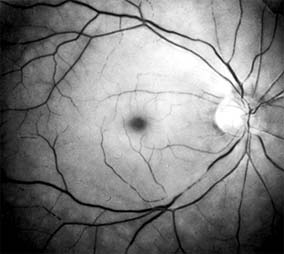

Diabetic retinopathy is a progressive microangiopathy characterized by small vessel damage and occlusion. The earliest pathologic changes are thickening of the capillary endothelial basement membrane and reduction of the number of pericytes. Background diabetic retinopathy is a clinical reflection of the hyperpermeability and incompetence of involved vessels. The capillaries develop tiny dot-like outpouchings called microaneurysms, while the retinal veins become dilated and tortuous (Figure 10-20).

Figure 10-20

Figure 10-20: Background diabetic retinopathy with abundant macular exudate (open arrow), micro-aneurysms (small arrow), and intraretinal hemorrhage (large arrow).

Multiple hemorrhages may appear throughout different levels of the retina. Flame-shaped hemorrhages are so shaped because of their location within the horizontally oriented nerve fiber layer, while dot and blot hemorrhages are in the deeper retina, where cells and axons are vertically oriented.

Macular edema is the most frequent cause of visual loss among patients with background diabetic retinopathy. The edema is caused primarily by a breakdown of the inner blood-retinal barrier at the level of the retinal capillary endothelium, allowing leakage of fluid and plasma constituents into the surrounding retina. The edema may be focal or diffuse and appears clinically as thickened, cloudy retina with associated microaneurysms and intraretinal exudate. Circinate zones of yellow, lipid-rich exudate may form around clusters of microaneurysms and are most frequently centered in the temporal portion of the macula. While the prevalence of macular edema is 10% in the diabetic population as a whole, there is a dramatic increase in prevalence in eyes with more severe retinopathy.